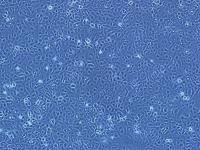

我司HS776T(人胰腺癌细胞)是细胞专业的供应商,竭力为您提供的产品和售后服务,保障您科研工作的顺利进行,欢迎您询价订购。

HS776T(人胰腺癌细胞)